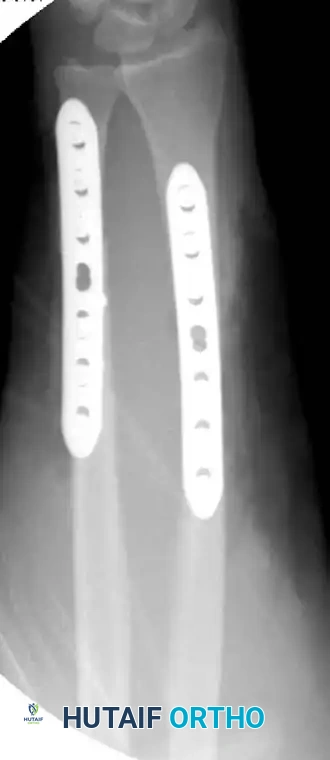

Figure 57-82A: Preoperative AP radiograph of a displaced both-bone forearm fracture in an adult.

Figure 57-82B: Preoperative lateral radiograph demonstrating significant translation and loss of the radial bow.

Figure 57-82C: Postoperative AP radiograph demonstrating anatomical reduction and rigid fixation with 3.5-mm compression plates.

Figure 57-82D: Postoperative lateral radiograph confirming restoration of alignment and appropriate plate contouring.